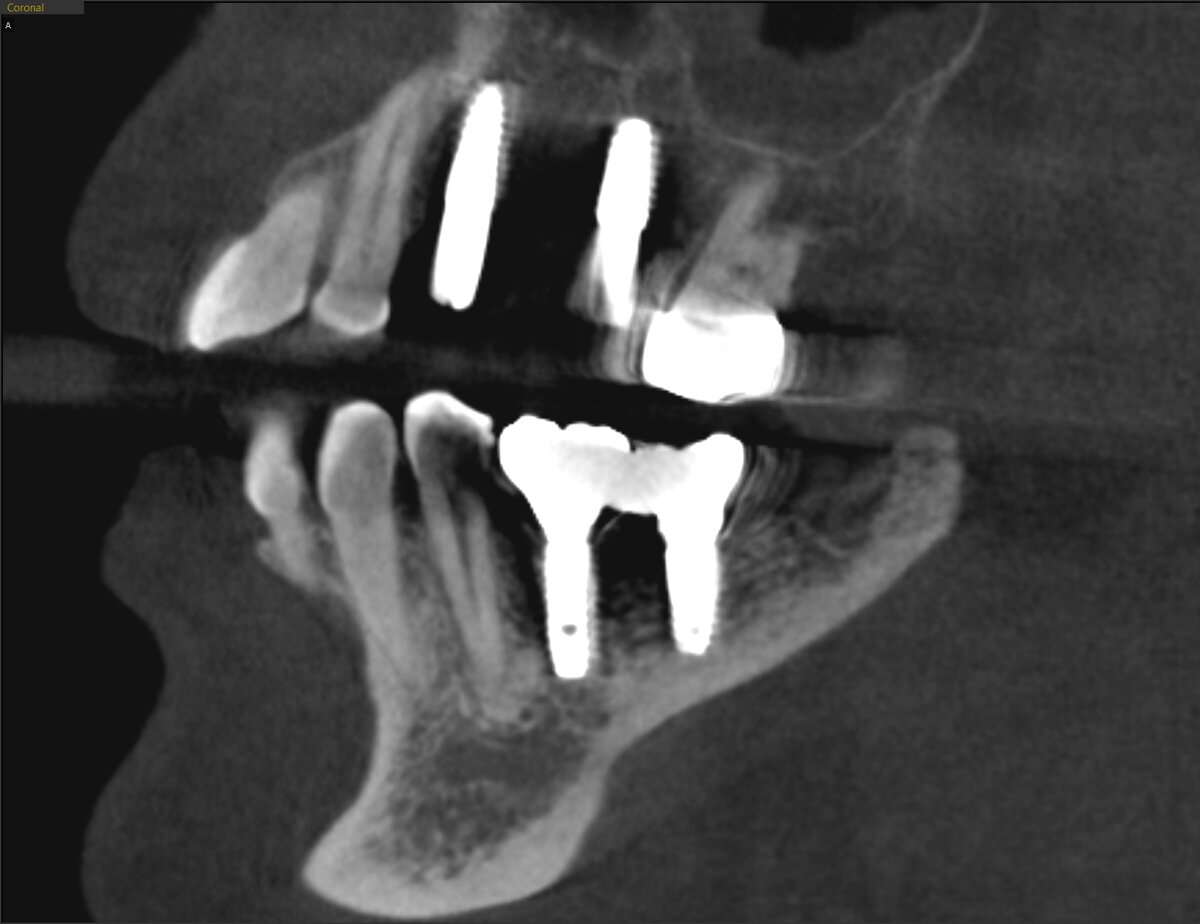

Делаем КЛКТ. Листайте - там срез.

Заранее не пугайтесь - чёрное это не всегда проблема, часто это артефакт, отсвет от металла. На всякий случай делаем прицельный снимок имплантатов нижней челюсти.

Проблема реальна - деструкция кости значительна и нам не померещилось. Но это совсем другая история. Сегодня разбор свежих имплантатов на верхней челюсти.

Слева отсутствуют 3 зуба - 4, 5 и 6. Зуб 7 на месте, но подвинулся в сторону отсутствующих собратьев.

Постановка:

Если работа проводилась по шаблонам, то зачем всё вот это? Ладно, косо - не проблема. А зачем так прижиматься к родным зубам?

Имплантат, который замещает 4-ку (у клыка расположен):

Имплантат, замещающий 6-й зуб (прижался к 7-ке):

Это всё бы ничего, но влияет на расположение будущих коронок:

4-ка ещё сносно, не буду ворчать. Но 6 - компромиссная история.

Чуть другой угол, нёбно много места и это безопасно - была бы конфета.